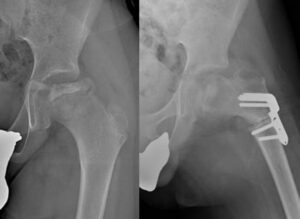

Per mantenere la testa femorale centrata nell’acetabolo, il chirurgo ortopedico dovrà valutare la procedura chirurgica migliore (osteotomia del femore o di bacino) per ottenere la migliore centrazione del femore. Ogni procedura include vantaggi e svantaggi, che il chirurgo ortopedico dovrà conoscere bene e discutere con la famiglia.

In qualche caso di morbo di Perthes verrà preso in considerazione un intervento minore di allungamento dei muscoli retratti o un’artrografia dinamica (cioè l’iniezione di mezzo di contrasto in articolazione) per valutare meglio se la testa del femore ha la possibilità di centrarsi o meno.